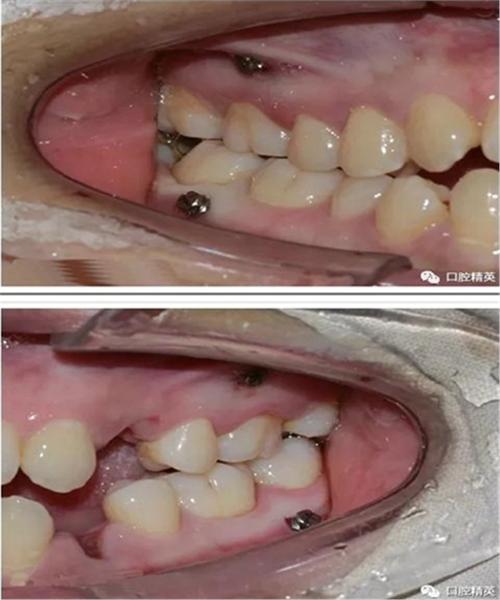

正畸微种植钉植入图片中,操作步骤、解剖结构识别与关键技术要点如何通过影像呈现?-图1

(图片来源网络,侵删)